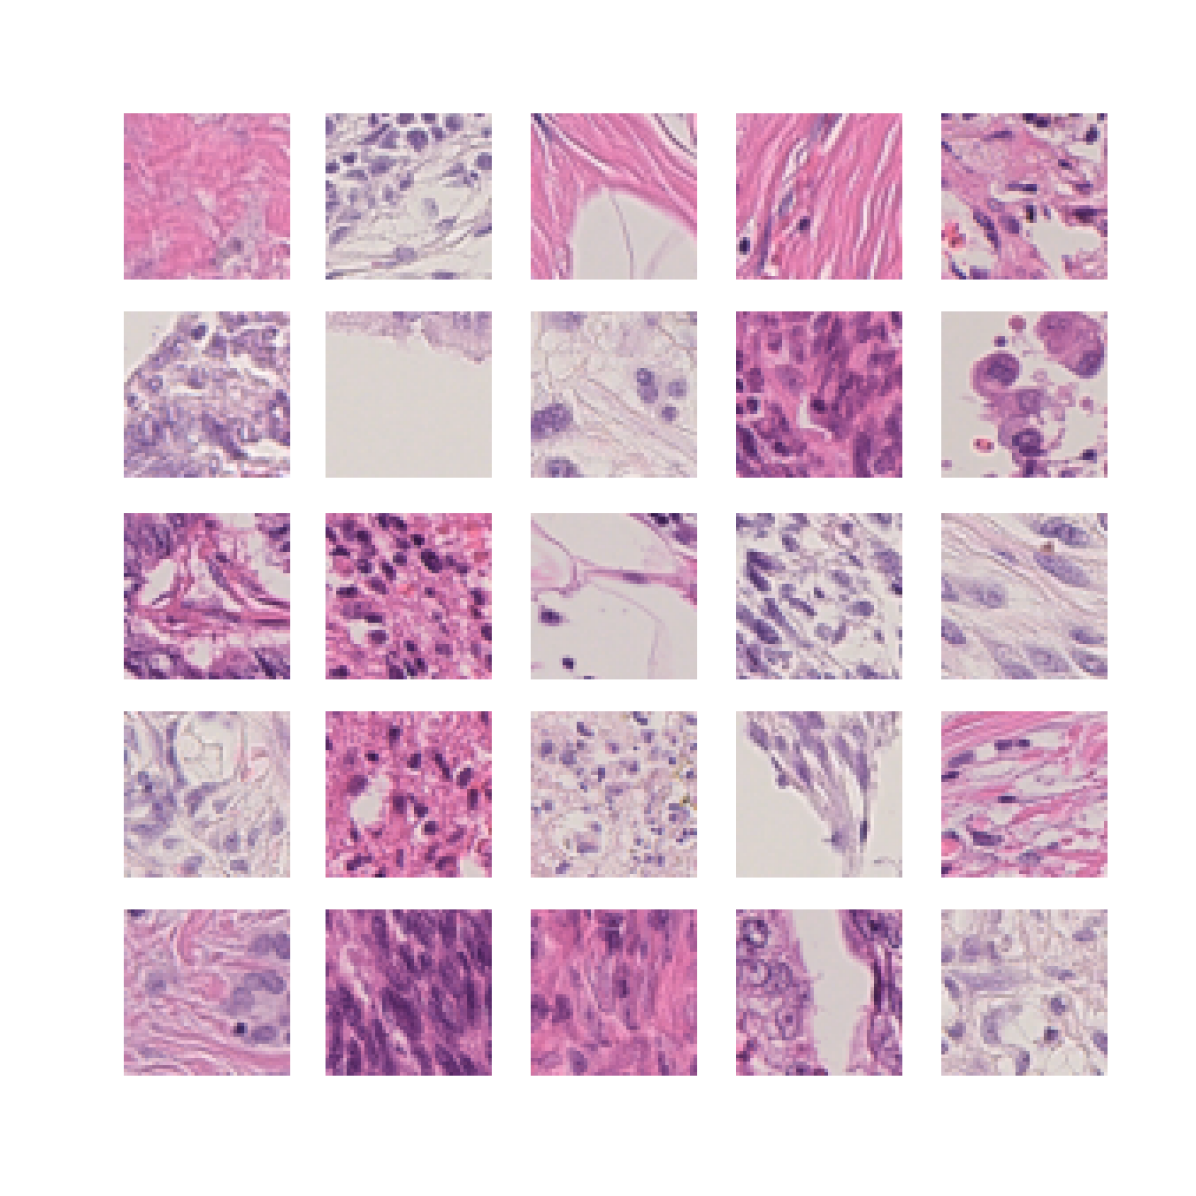

We also analyse the activation maps for each model using GradCAM as described in section S3. This offers more insight into the areas of the image which are contributing most heavily to the models’ representations. In Figure 4(b) we present some representative examples, however, a larger selection which was chosen at random is presented in Figures S10 to S25. The larger selection makes it easier to see the emergent patterns, including that privileged Siamese models tend to mainly identify features which are strongly present in both inputs, while unprivileged Siamese models tend to learn more diffuse features that are not specific to one cell phenotype or image region. TriDeNT ♆ incorporates both sets of features, learning both features specific to the privileged data and more the general features associated with unprivileged Siamese networks.

We can see in Figure 4(b) panel A that for ERG, the privileged Siamese model focuses almost exclusively on any nuclei which could be endothelial cells. As there are very few endothelial cells in the dataset, it could be an effective strategy to identify anything that could potentially be an endothelial cell to minimise the difference between the representations of the H&E model and the IF mask model. In the corresponding unprivileged Siamese image, we see that the model identifies some of these nuclei, albeit less strongly, but also focuses heavily on the other tissue and even the background, while strongly fixating on two spots of debris in the center of the image. This model has less ‘incentive’ to learn the weak features related to endothelial cells as these occur rarely and are not easy to detect, while more generic strong features such as the presence of connective tissue and the prevalence of background are more common and predictable from augmented images. We see that TriDeNT ♆ combines these two feature sets, strongly identifying nuclei while also identifying the connective tissue.

In panel C we see a similar pattern, with the privileged Siamese model fixating solely on the nuclei, while the TriDeNT ♆ model takes a more balanced approach. The unprivileged Siamese model appears to focus on a single cluster of nuclei while neglecting others, and similarly identifies an area of fibroblasts with its distinctive pattern but does not others.

In contrast to panels A and C which represent models with poor privileged Siamese results, panels B and D represent models whose privileged Siamese results were comparable to both TriDeNT ♆ and even the supervised baseline. It is therefore interesting to note that there are far more similarities between the privileged Siamese and TriDeNT ♆ models in both cases. Particularly in panel B, TriDeNT ♆ and the privileged Siamese model return virtually identical heatmaps, with both strongly identifying epithelial nuclei and neglecting the same areas of connective tissue. The unprivileged model in this case appears to focus solely on the centre of the image, giving a significantly different heatmap to the other panels.

Panel D again shows the previous pattern, with the privileged Siamese model identifying the features strongly present in the privileged data – fibroblasts – while neglecting the nuclei present. TriDeNT ♆ also strongly identifies the connective tissue, but, unlike the privileged Siamese model, does not completely neglect the nuclei. The unprivileged Siamese model primarily identifies background, and does not appear to identify the nuclei in this example.